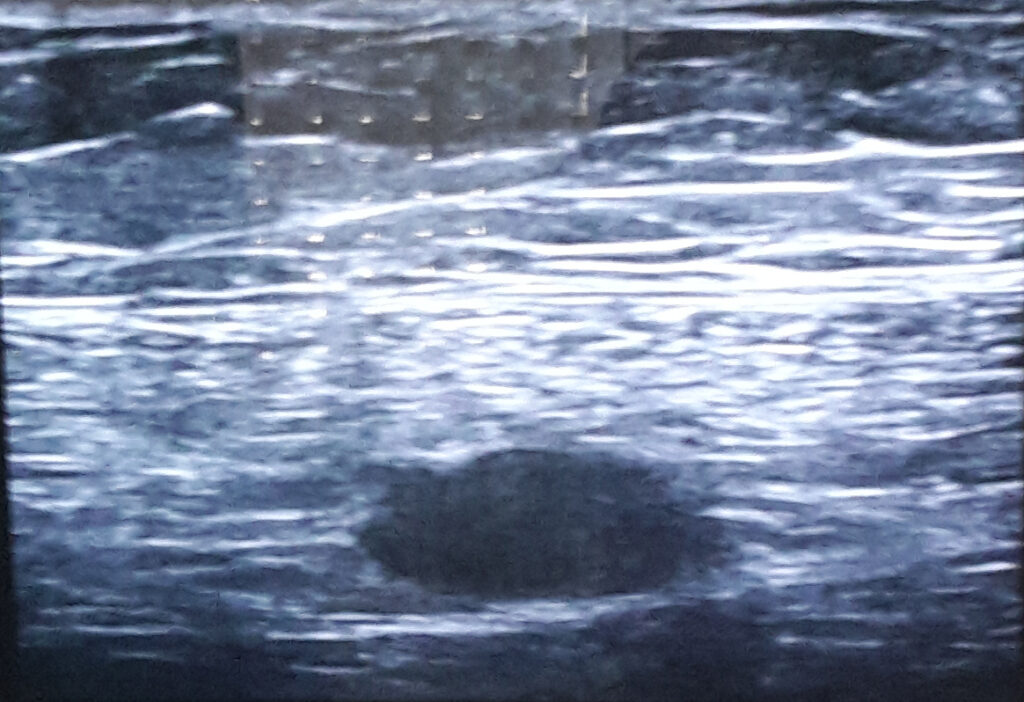

So lag ich dann auf der Liege und guckte zu wie sie den Ultraschall machte. Es dauerte eine Weile bis sie den Kerl fand. Als sie das Gebilde vermass, stellten wir fest, dass er nach nur ein paar Tagen wieder kleiner geworden ist. „Der schmilzt ja wie Butter in der Sonne“ freute sich die Ärztin. Da warten wir noch einen Monat und gucken dann nochmal. Denn die Stelle wo der sitzt ist nicht einfach zu operieren. Und wenn wir den Tumor mit den Tabletten wegbekommen ists ja wunderbar.

Hier ist dieses Mistding, das mir die letzten Tage so Kummer bereitet hat. Jetzt ist der Tumor noch 1,4 cm gross. Er war einmal über 2 cm. Also lassen wir ihn schmelzen und ertragen die unangenehmen Nebenwirkungen der Tablette. Ein bisschen Gliederschmerzen, die ich allerdings schon von meiner Fibromyalgie kenne. Ein bisschen mehr oder weniger Kopfschmerzen und ein bisschen Stimmungsschwankungen. All das, so hoffe ich, wird sich geben, wenn mein Körper sich daran gewöhnt hat, daran gehindert zu werden Östrogen zu produzieren.